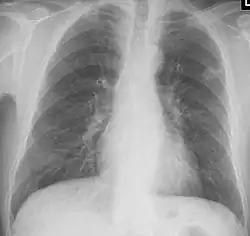

In der Medizin dient das Röntgen zur Feststellung von Anomalien im Körper, die im Zusammenhang mit Symptomen, Zeichen und eventuell anderen Untersuchungen eine Diagnose ermöglichen (Röntgendiagnostik). Die unterschiedlich dichten Gewebe des menschlichen (oder tierischen) Körpers absorbieren die Röntgenstrahlen unterschiedlich stark, so dass man eine Abbildung des Körperinneren erreicht (Verschattung, Aufhellung und andere Röntgenzeichen). Das Verfahren wird zum Beispiel häufig bei Verdacht auf einen Knochenbruch angewendet: Zeigt das Röntgenbild eine Unterbrechung der Kontinuität des Knochens, ist der Verdacht bestätigt.

Je weicher die Strahlung (niedrige kV-Werte) ist, desto größer ist der Anteil der vom Gewebe absorbierten Strahlung. Dadurch werden auch feinste Gewebeunterschiede auf dem Röntgenfilm sichtbar gemacht. Dies ist der Fall bei der Mammografie (Röntgenuntersuchung des Brustgewebes), jedoch ist die Strahlenbelastung des durchstrahlten Gewebes dadurch relativ hoch. Harte Strahlung (über 100 kV) durchdringt Gewebe und Materialien (Gips und sogar Bleischürzen von geringerer Dicke) wesentlich leichter. Kontrastunterschiede werden stark abgemildert, wie z. B. bei Lungenaufnahmen (120 kV), bei denen sonst im Bereich der Rippen keine Beurteilung der Lungenstruktur möglich wäre.